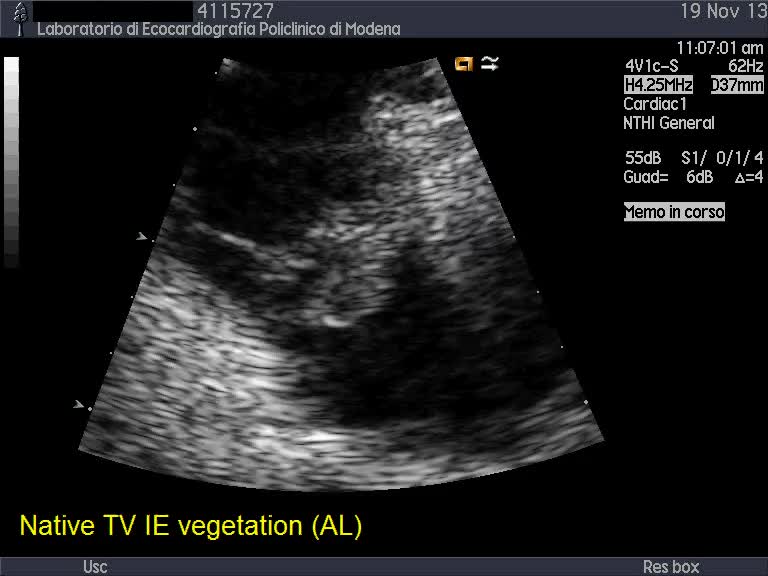

Endocardite infettiva della valvola tricuspide

Autore:

Andrea Barbieri